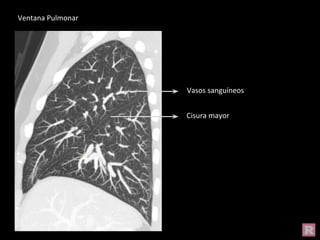

Ventana Pulmonar

Vasos sanguíneos

Cisura mayor